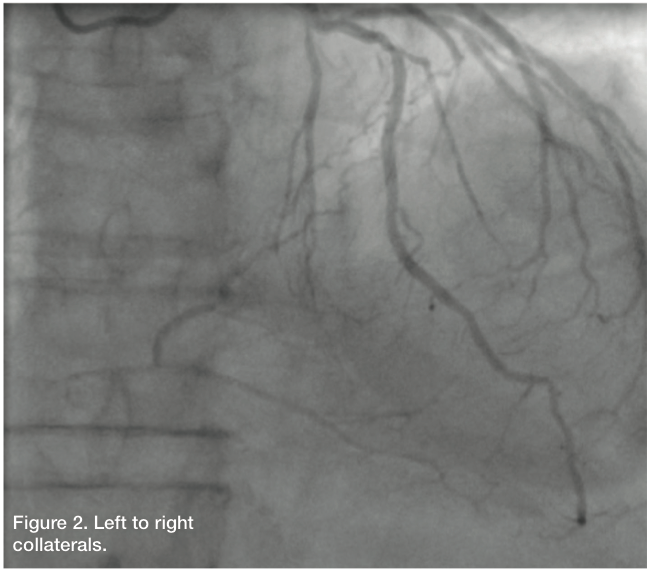

Right coronary artery (RCA): The RCA is 100% occluded. It is diffusely diseased in its proximal and mid portion with mid 100% occlusion. There is evidence of left to right collaterals.

Giving the patient’s angiographic findings, we elected to intervene on the RCA. We upsized the sheath to a 6 Fr Glidesheath in the right radial artery and used an Amplatz left (AL) 1 guide catheter to engage the RCA. We accessed the left radial with a 5 Fr for a contralateral injection and used a 5 Fr JL4 guide catheter from the left radial. Bivalirudin (Angiomax, The Medicines Company) was administered, and using a 1.25 mm over-the-wire balloon and an Asahi Fielder wire (Abbott Vascular), we attempted to navigate the RCA. The wire kept deflecting into a side branch, although there seemed to be, at least on initial angiography, a “beak.” The wire continued to deflect into a side branch. Additional wires were then used, including a Pilot 150 wire (Abbott Vascular) and a Miracle Bros 3 wire (Abbott Vascular), both of which were unsuccessful. At this time, we elected to attempt a retrograde approach via a transcollateral. Left to right collaterals from the circumflex appeared to offer the most direct path. We wired into the LCX artery, but there was poor visualization trying to inject around the 5 Fr sheath. Therefore, we pulled everything, and upsized to a 6 Fr JL4 guide catheter.